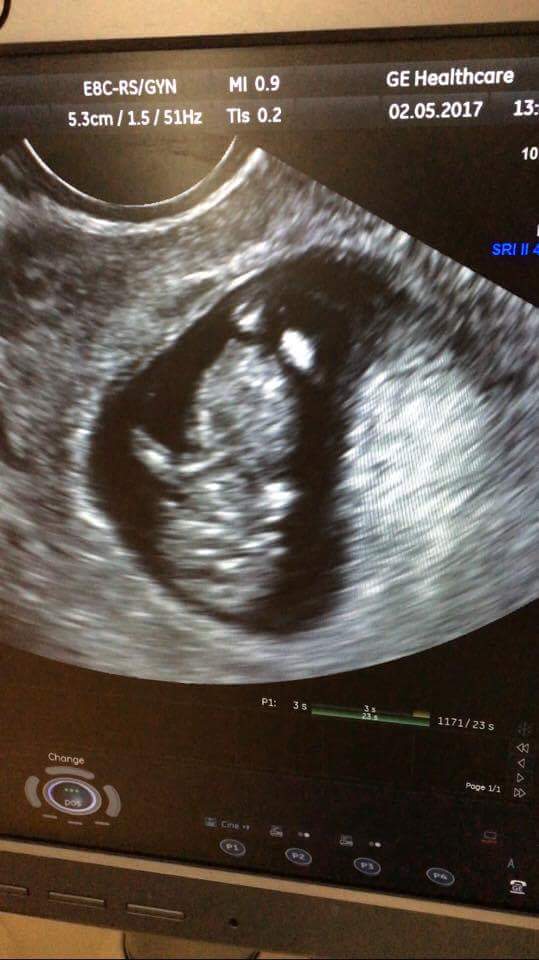

Super dzidzia gratulacje☺Zobacz załącznik 804782 Zobacz załącznik 804783 Zobacz załącznik 804784

My po wizycie

Na pierwszym zdjęciu widać rączkę, na drugim rączki, nóżki, na trzecim jest do góry nogami. Ruszał się, wręcz tańczył, serduszko tłucze jak szalone. Wszystko jest pięknie! Lekarz zachwycony, a my przeszczęśliwi![]()